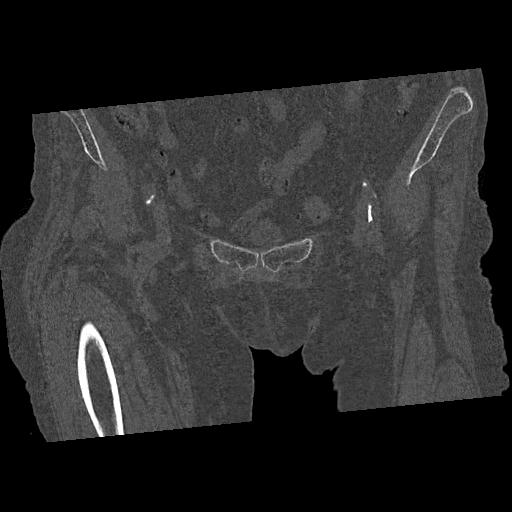

100703 1/27 両股正面+軸 1/29 両股正面+軸 94歳女性 パンソンロン